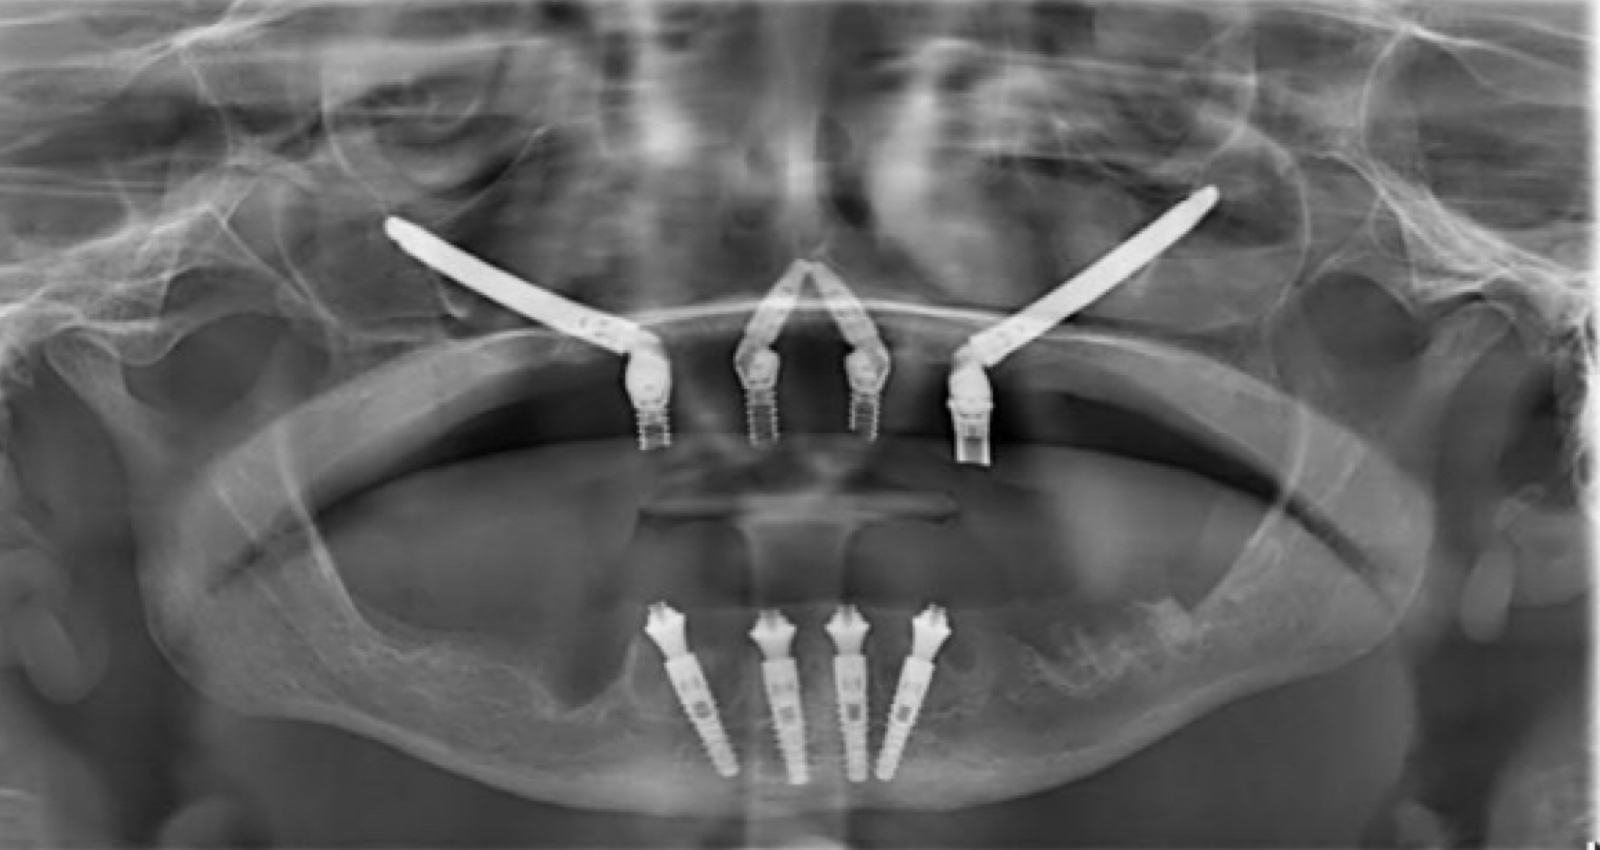

A implantodontia é um procedimento odontológico que envolve a colocação de implantes dentários de titânio no osso maxilar ou mandibular para substituir dentes perdidos. Os implantes proporcionam uma base sólida para a fixação de coroas, pontes ou próteses, restaurando a função mastigatória, estética e saúde bucal do paciente.